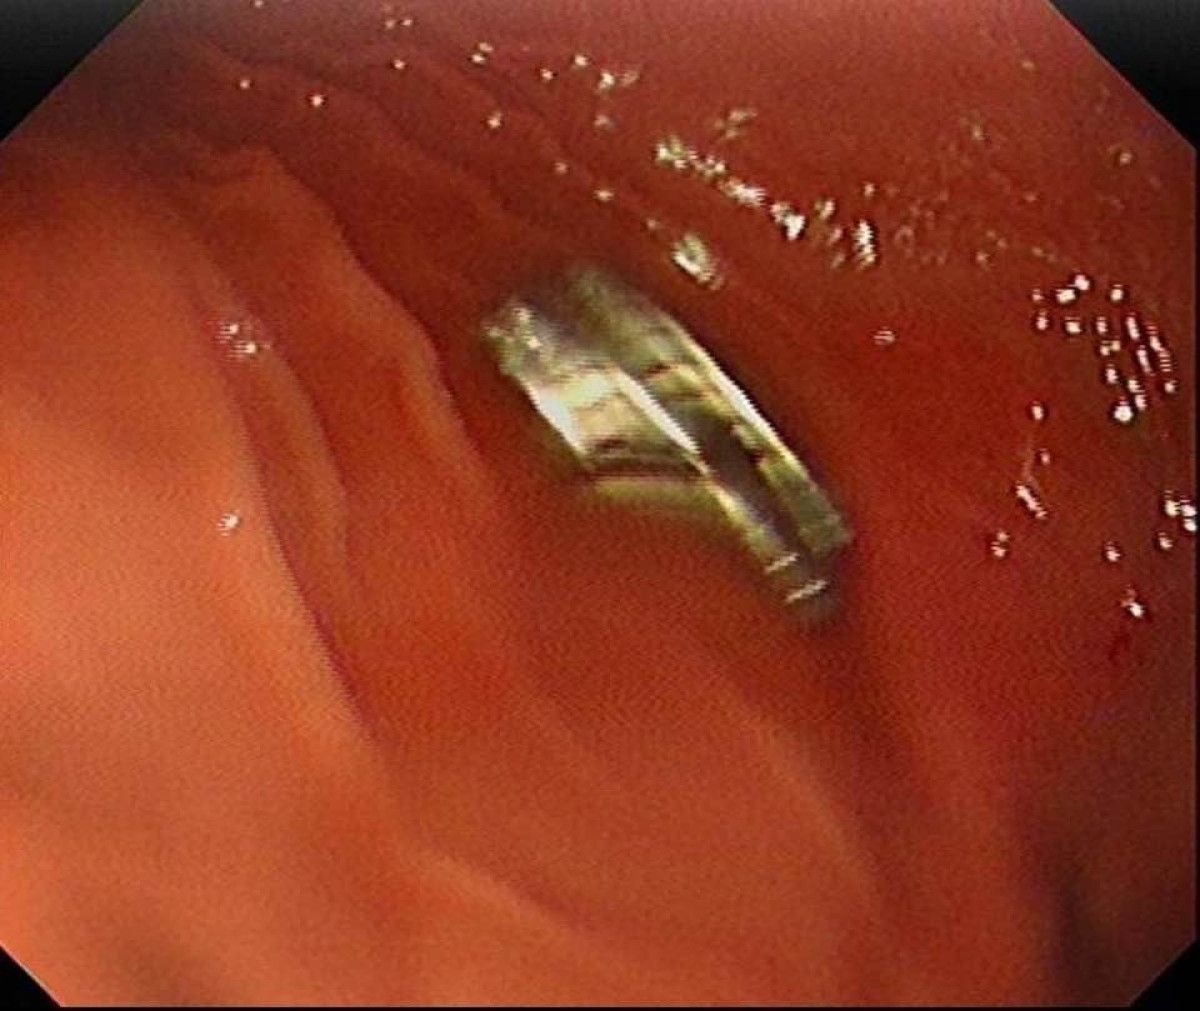

Fırat Üniversitesi Çocuk Gastroenteroloji Hepatoloji ve Beslenme Bilim Dalı Başkanı Prof. Dr. Yaşar Doğan, çocuk hastanın yemek borusuna yapışmış 19 mıknatısı endoskopik yöntemle çıkardı.

Mıknatıslar uzun süre yemek borusunda takılı kaldığı için yemek borusu ve mide girişinde zedelenmeler olurken, çocuğun sağlık durumunun iyi olduğu ve taburcu edildiği öğrenildi.